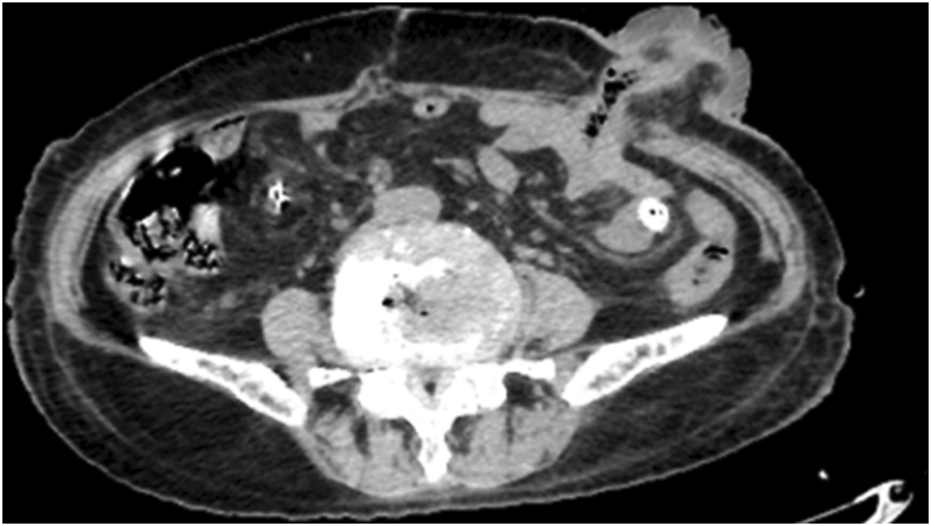

A 79-year-old female lung cancer patient presented with persistent abdominal colic lasting 7 hours. Her physical examination findings were as follows: body temperature of 37.7°C, heart rate of 98 beats per minute, and blood pressure (BP) of 117/90 mmHg. The blood test results were as follows: white blood cell (WBC) count of 9.3 × 109/L (normal: 4.0–10.0 × 109/L); neutrophil (NE) count of 8.16 × 109/L (normal: 2.0–7.0 × 109/L); and C-reactive protein (CRP) level of 36.03 mg/L (normal: 0–10 mg/L). Her liver and kidney functions were normal. Whole-abdominal CT imaging indicated a possible perforation in the digestive tract (Figure 1). During laparotomy, a 5.0 cm perforation was identified in the descending colon near the splenic flexure; no palpable tumor or lymphadenopathy was observed. Surgical intervention involved partial resection of the descending colon with transverse colostomy, and specimens from the resected colon and greater omentum were collected for pathological analysis.

FIGURE 1

Abdominal computed tomography (CT) revealed mild thickening of the descending colon wall accompanied by free gas and surrounding exudation, a perforation of the digestive tract was considered.